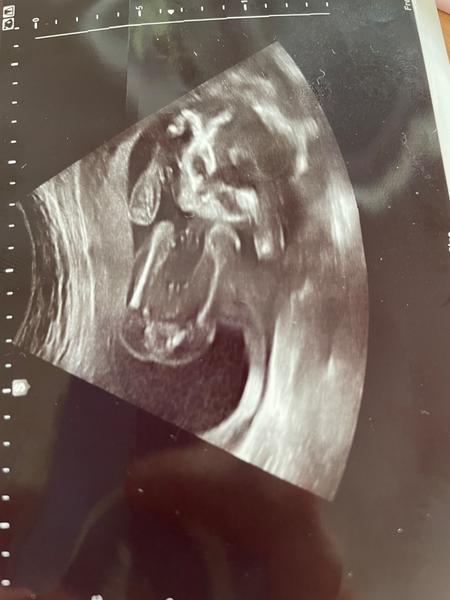

Chlapec nebo děvče?

chtěla bych se zeptat na pohlaví miminka.

Je možné rozpoznat z ultrazvukového snímku?

z těchto fotografií to odhadnout nelze, rovina řezu není ta správná. ☹